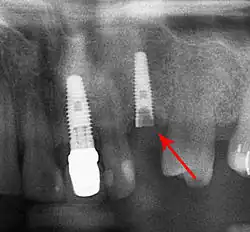

Beyond the possibility of mechanical failure[98] which may be due to poor prosthetic fitment, wear and tear, or user-induced actions such as bruxism, dental implants are also subject to peri-implant mucositis and peri-implantitis, where gum tissue and bone mass around the implant are resorbed, and the implant gradually becomes loose, and has to be removed.[99][100] In addition, although titanium is generally well tolerated by the body, there have been cases where the build-up of titanium particles released by the implant may cause systemic inflammatory response.[101] Because there is no dental enamel on an implant, it does not fail due to cavities like natural teeth. While large-scale, long-term studies are scarce, several systematic reviews estimate the long-term (five to ten years) survival of dental implants at 93–98 percent depending on their clinical use.[15][16][17] During initial development of implant retained teeth, all crowns were attached to the teeth with screws, but more recent advancements have allowed placement of crowns on the abutments with dental cement (akin to placing a crown on a tooth). This has created the potential for cement, that escapes from under the crown during cementation to get caught in the gingiva and create a peri-implantitis (see picture below). While the complication can occur, there does not appear to be any additional peri-implantitis in cement-retained crowns compared to screw-retained crowns overall.[102] In compound implants (two stage implants), between the actual implant and the superstructure (abutment) are gaps and cavities into which bacteria can penetrate from the oral cavity. Later these bacteria will return into the adjacent tissue and can cause periimplantitis.